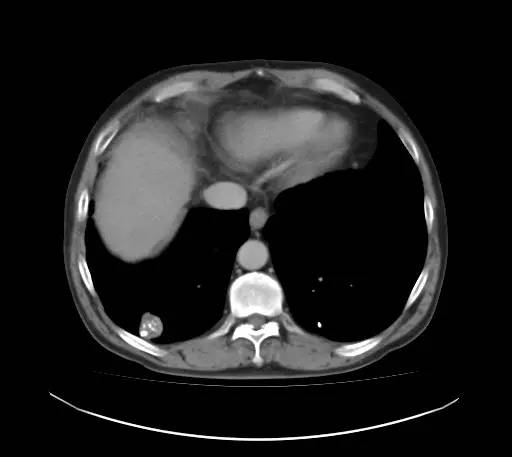

男,52岁,查体发现肺部病变

[影像描述]

右肺下叶结节样病变,内有钙化、脂肪成分,增强后可见轻度强化。

[检查结果]

右肺下叶错构瘤.

右肺下叶病变内有钙化、脂肪成分,典型爆米花样钙化,增强后可见轻度强化。